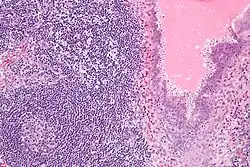

Endosalpingiosis is diagnosed by a pathologist on excision (e.g. biopsy).

It is characterized by cysts with tubal-type epithelium (e.g. ciliated epithelium) surrounded by a fibrous stroma. It is not often associated with hemorrhage.

A tubal-type epithelium surrounded by endometrial-type stroma is a variant of endometriosis, not endosalpingiosis.

Endosalpingiosis is occasionally found in lymph nodes, and may be misinterpreted as an adenocarcinoma metastasis.[5]